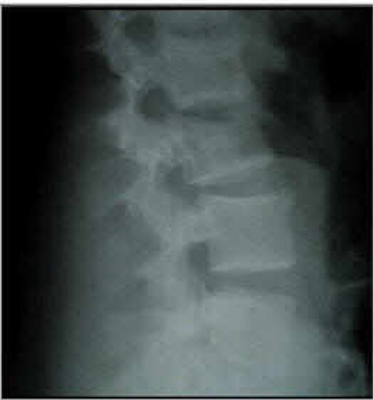

8. A 49-year-old male fell from a height of 10 feet while cleaning his roof. He sustained the isolated injury shown in Figures A and B. Upon transfer from the outside hospital 10 hours later, he has 0/5 motor strength in bilateral lower extremities, no sensation distal to umbilicus, and an intact bulbocavernosous reflex. He has no perianal sensation or rectal tone. He received no medical management at the outside hospital. Which of the following is the most appropriate use of methylprednisolone in this patient.?

FIGURES: A

B

DISCUSSION: The clinical presentation describes a lower thoracic spine burst fracture with a complete neurological spinal cord injury. Since the patient's injury occurred ten hours prior to presentation, data does not support initiation of high-dose methylprednisolone.

Figures A and B are the sagittal and axial CT cuts that show a T9 burst fracture with rotational malalignment and moderate retrolisthesis.